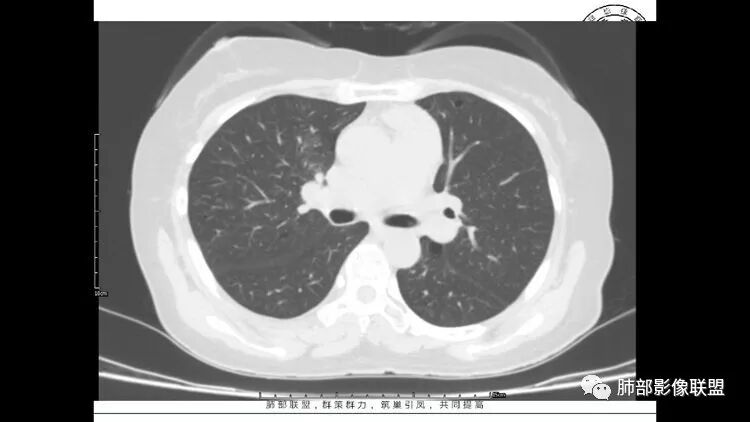

胸CT:1.双肺多发囊性变,以中下肺为主,病变边缘可见肺动脉,部分囊内可见分隔及肺动脉,双下部分肺野周围可见小叶中心结节及树丫征。

2 左肺上叶尖后段 右肺上叶前段 右肺下叶外基底段 结节影,边界清楚,可见柔软毛刺,左肺下叶后基底段混合密度影。

3.纵隔淋巴结肿大?,以主动脉弓为界向上向下增大。

患者中年女性,因右眼红痛1天就诊。胸CT:双肺多发囊性变及结节影,囊以中下肺为多,部分囊内可见分隔及肺动脉,结节部分为实性,部分为混合性,边缘光滑,未见明显毛刺、棘突、胸膜牵拉及血管集束征象。双中下可见支气管扩张及树丫征。淋巴结无明显肿大。综合考虑:一元淋巴细胞间质性肺炎。多元鉴别肺腺癌并转移等恶性病变。

双肺下叶分布为主的间质改变(磨玻璃影、小叶间隔增厚)、散在气囊影(常有血管贴边)、边界不清小结节